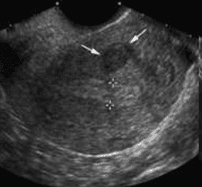

U xơ cơ tử cung thành trước tử cung

U xơ cơ tử cung thành sau tử cung dưới thanh mạc, tăng âm do thành phần xơ nhiều hơn cơ